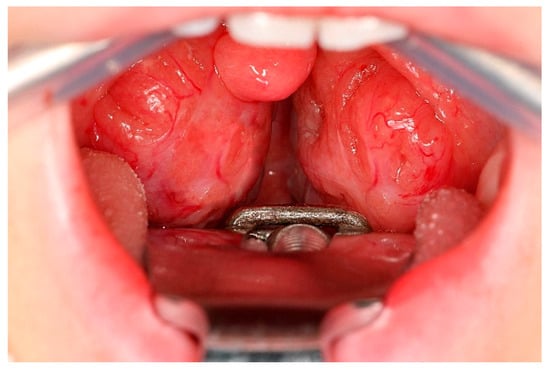

- On the other hand, children with obstructive sleep apnea may experience a significant impairment in their quality of life and negative effects on their cognitive and emotional development.

3.9. Variations of Tonsillectomy